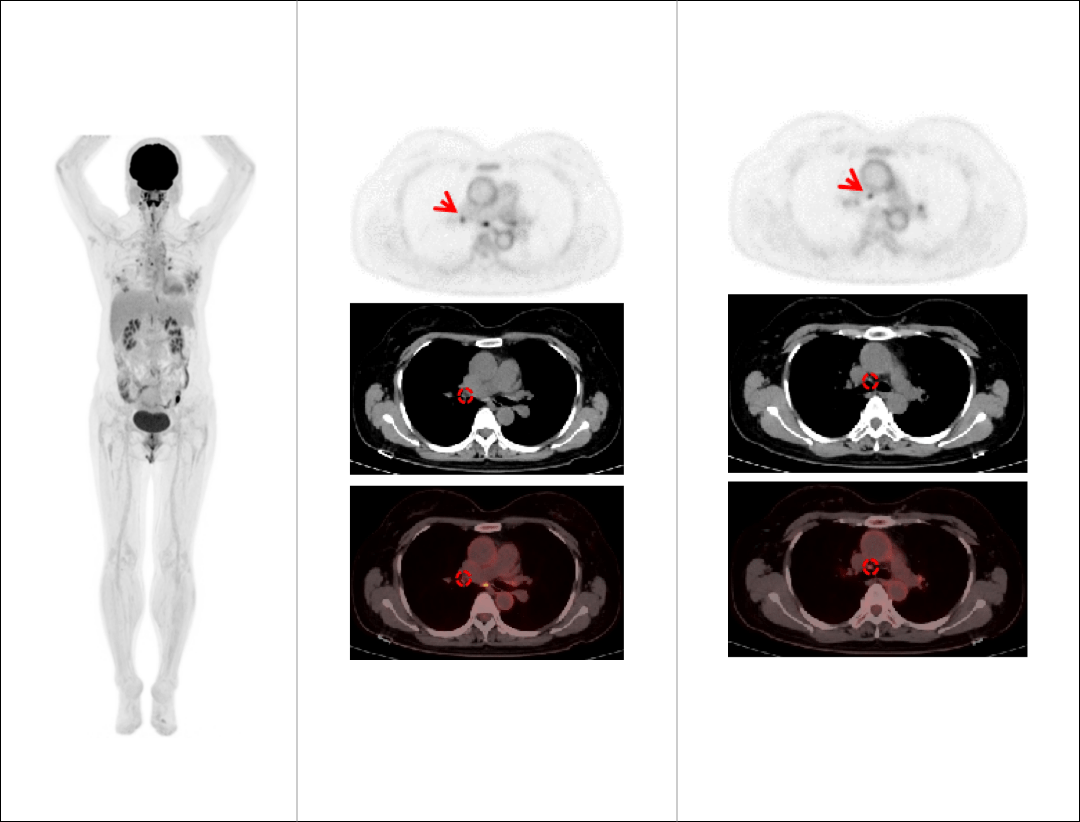

肺癌胸腹部单床位大范围延迟扫描